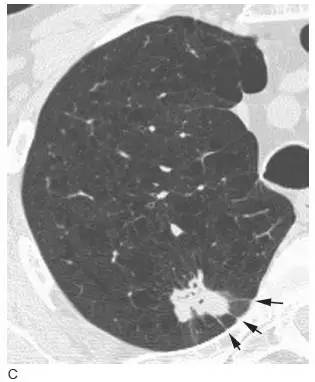

2、腺癌

在胸片上腺癌因其边缘不规则常表现为边缘显示不清( 图4A)。在高分辨率CT 上, 腺癌表现为圆形或分叶状的孤立结节。由于邻近肺浸润,其边缘常不规则呈毛刺边缘( 图4B)。当发生在胸膜下时,可表现为细线状延伸至胸膜面( 即胸膜尾)( 图4C)。CT 可显示结节内空气支气管征。虽然中央坏死很常见,但在平片或CT 上空洞并不常见。当腺癌起源于中央支气管壁时,影像学很难与鳞癌相鉴别。

图4 腺癌的典型表现

A. 腺癌患者胸片显示左肺尖边界不清的结节( 箭头), 在胸片上因病灶边界不规则和边缘毛刺,腺癌常表现边界模糊结节;

B. 左上叶腺癌患者高分辨率CT 显示左上叶孤立结节,边缘不规则伴毛刺。毛刺是由于肿瘤伴肺纤维所致。肿瘤分期为T1;

C. 腺癌患者高分辨率CT 上显示右上叶后段的孤立结节呈分叶状,边缘可见毛刺, 结节延伸至胸膜的表面( 箭头) 称胸膜尾征,由纤维束牵拉脏层胸膜表面而形成